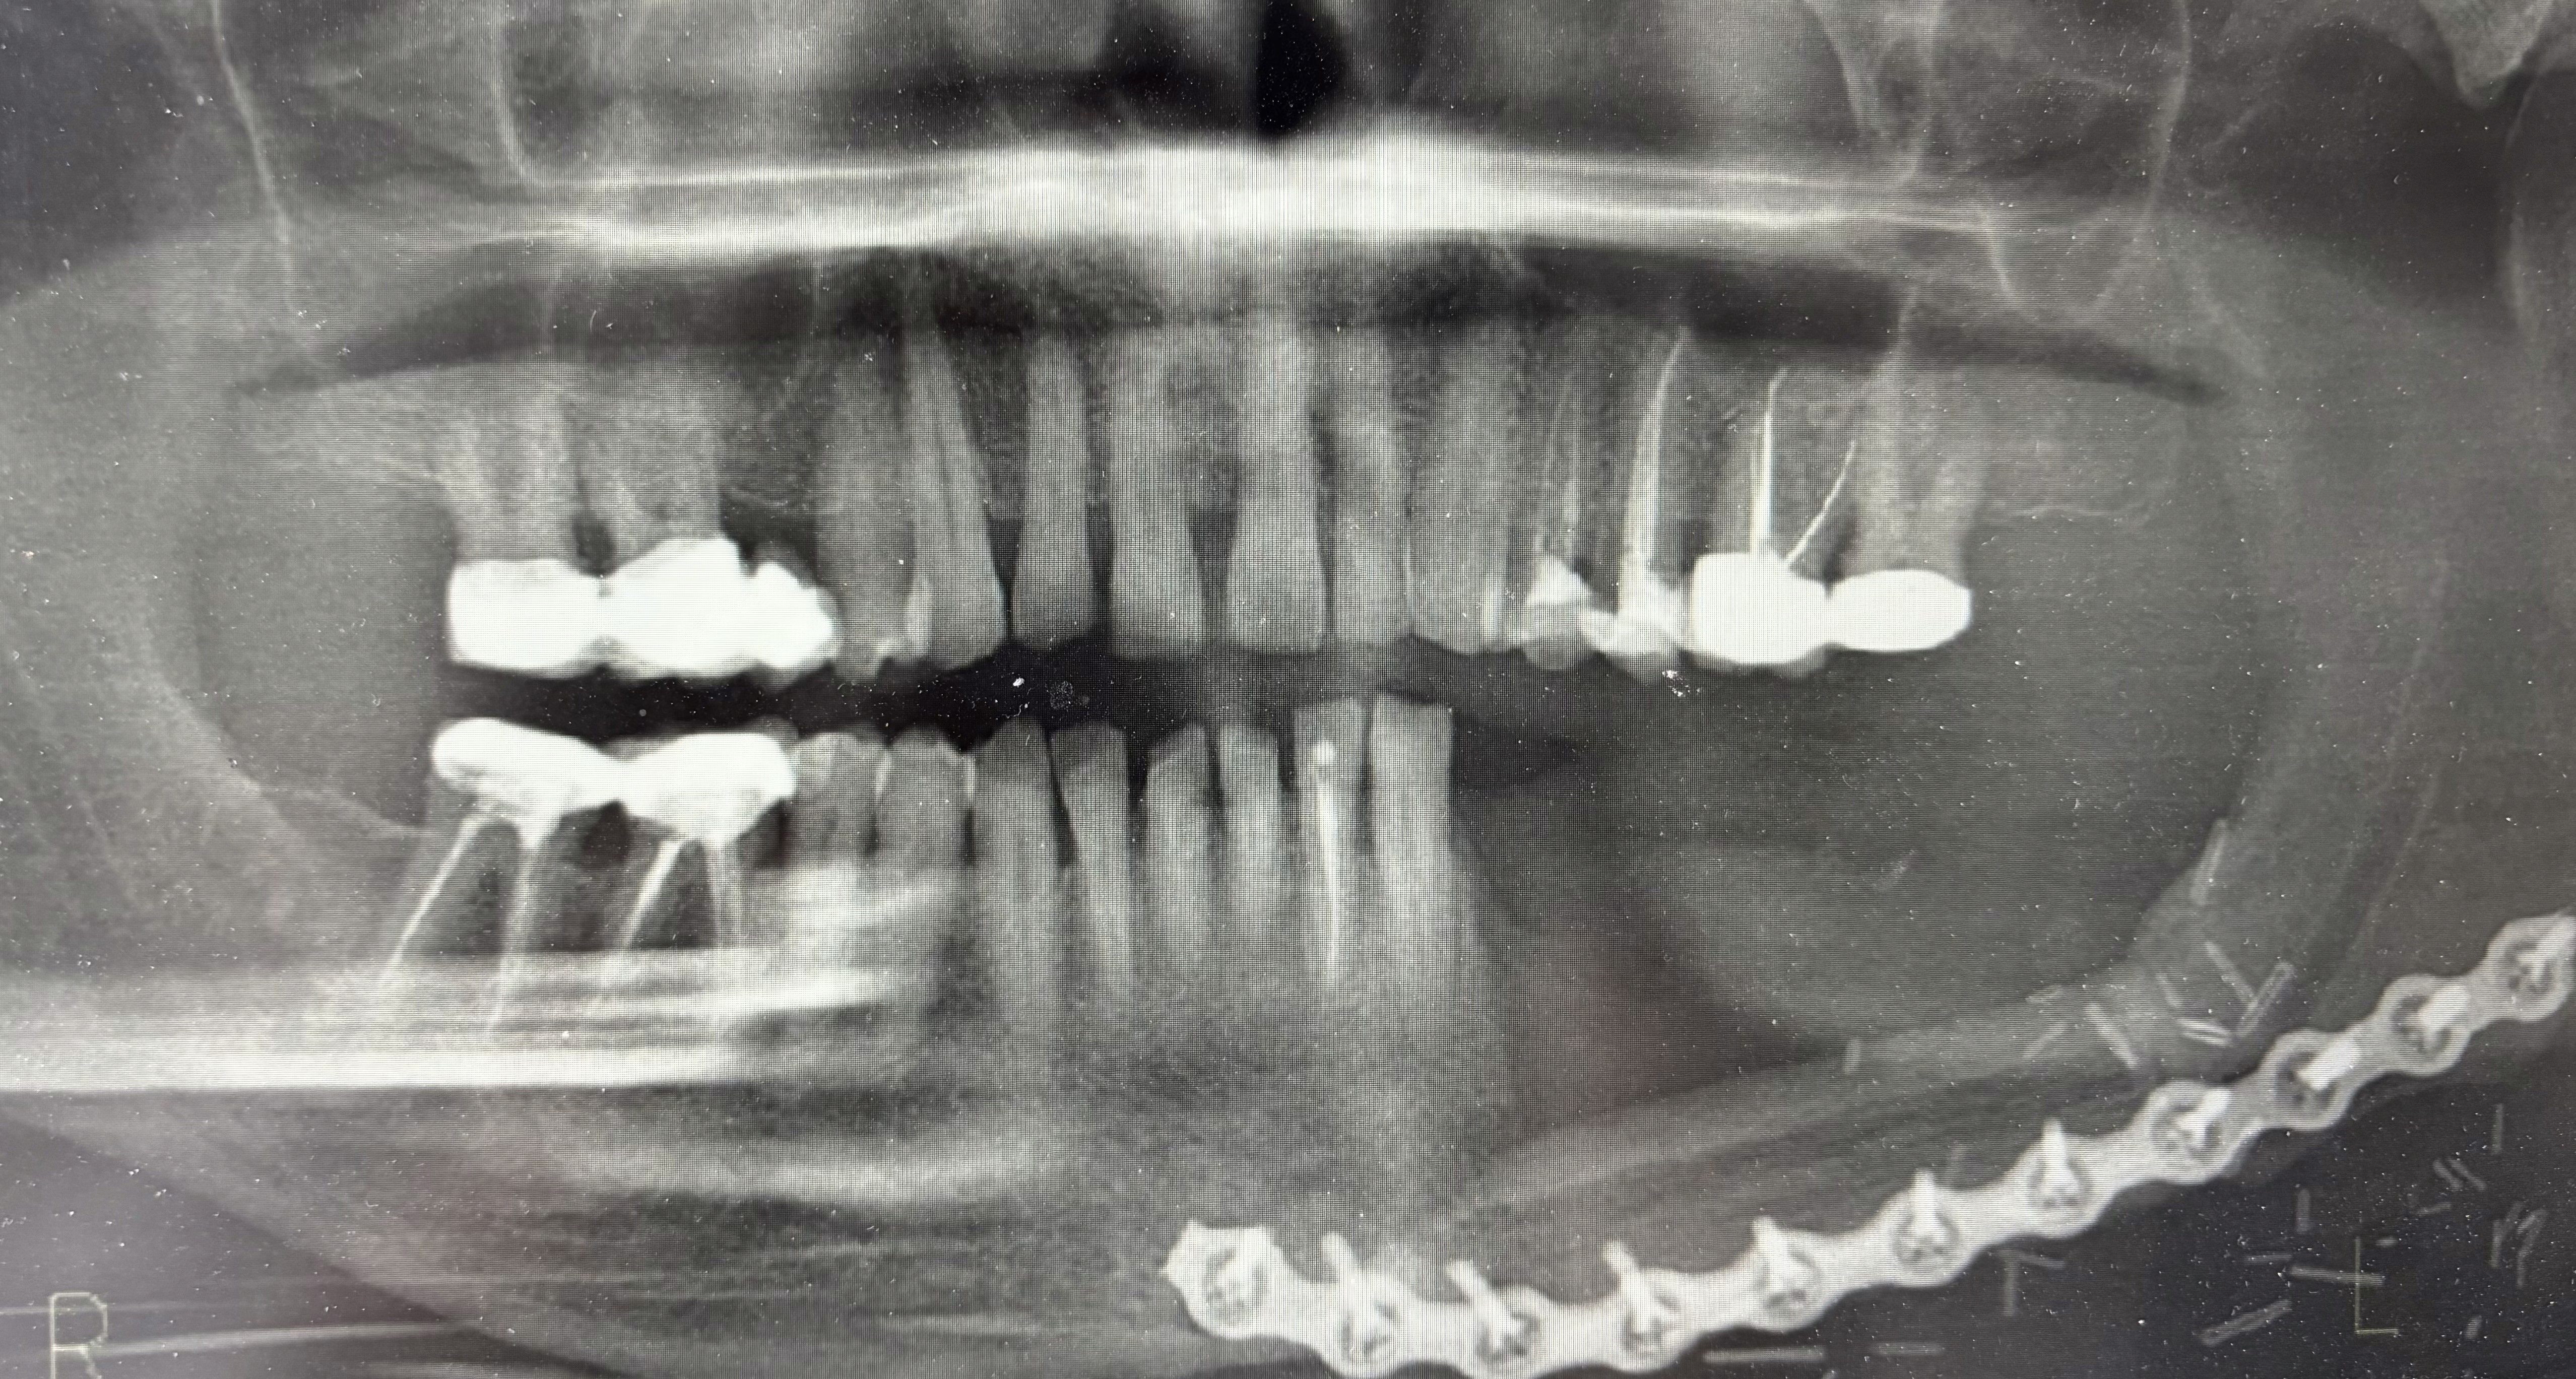

Insertion of distractor for placement of implants on a fibula flap post mandibula excision